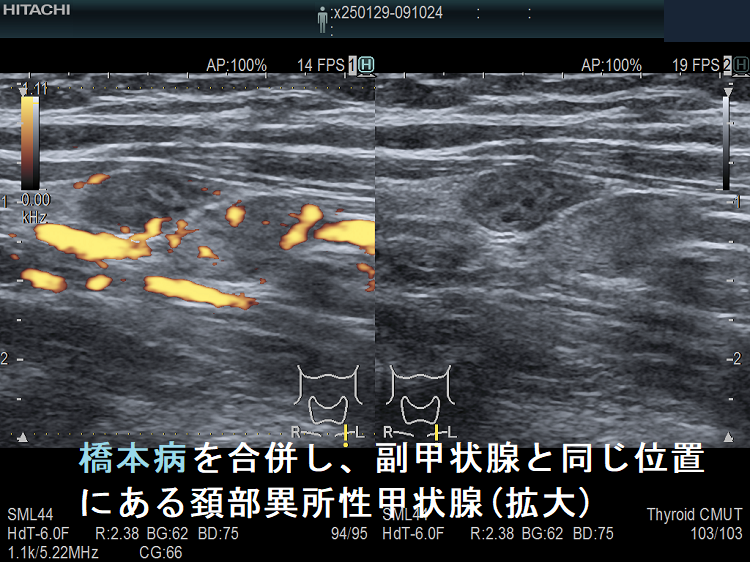

橋本病を合併し、副甲状腺と同じ位置にある頚部異所性甲状腺(拡大)ドプラーモード

橋本病を合併し、副甲状腺と同じ位置にある頚部異所性甲状腺 (拡大)ドプラーモード